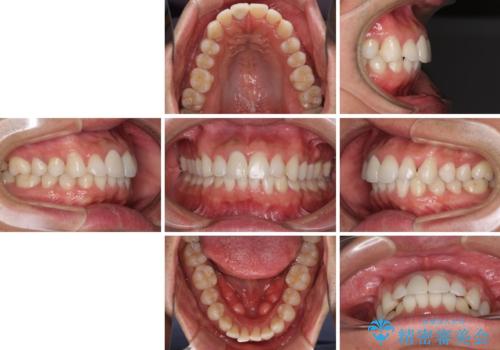

- 口の閉じにくさを気にして来院された患者様です。

患者様と相談の上、横顔の印象から抜歯矯正は必要ないと判断し、IPR(歯と歯の間)並びに歯列全体の後方移動により口元の突出感の改善することとしました。

しっかりと装着時間を守り、ゴムかけも徹底していただいたので、思いの外口元を引っ込めることができました。

これ以上の改善を望まれましたが、非抜歯矯正でこれ以上口元を引っ込めると食いしばりすやすい咬合となるため、この歯列で終了としました。